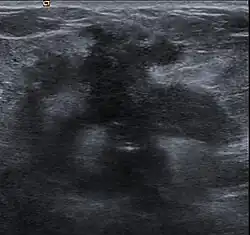

Desmoplastic small round cell tumour, with desmoplasia surrounding nests of cancer cells.